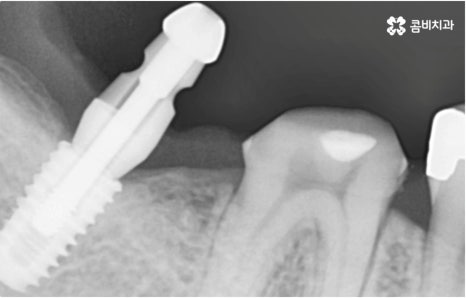

자연 치아를 살리기 위한 거의 마지막 단계의 보존 치료가 바로 신경치료, 재신경치료, 치근단절제술 등이며, 만약 치아재식술을 통해서도 살릴 수 없을 정도로 손상이 깊고 심하다면 해당 치아를 발치하고 임플란트를 통해 인공 치아로 대체해 줄 필요가 있습니다.

임플란트는 유치, 영구치 이후로 제 3의 치아라고 불리울 만큼 자연 치아의 상실에 대처하는 인공 치아 중에 가장 각광을 받고 있습니다. 저작력 회복이 80%에 가깝고 심미적으로 자신의 치아와 거의 다름없어 보이는 부분에서도 만족도가 높아 많은 분들이 찾고 있지만 식립 성공률과 안정적인 지속률에 크게 영향을 주는 올바른 위치 및 각도로의 식립을 무리하지 않게 진행하기 위해 술자의 높은 숙련도를 요하는 고난도의 수술이기 때문에 임상 경험이 많고 뛰어난 노하우를 갖추고 있는 담당의 선생님과 함께 하시는 것이 중요한 포인트라고 할 수 있어요.